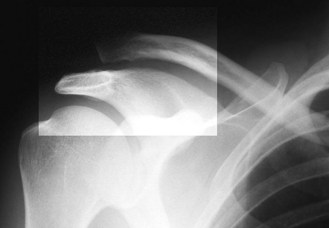

Osteoporosis is systemic skeletal loss of bone mineral density with associated microarchitectural deterioration. It is the most common cause of abnormal bone structure. The incidence increases with age, particularly in postmenopausal women (Box 14.27). In the absence of complications, osteoporosis is asymptomatic. Although any osteoporotic bone can fracture, common sites are the distal radius (Fig. 14.56), neck of femur (Fig. 14.43), proximal humerus and the spinal vertebrae. Caucasians in Europe have a lifetime risk of osteoporotic fracture of 50% in women and 20% in men.